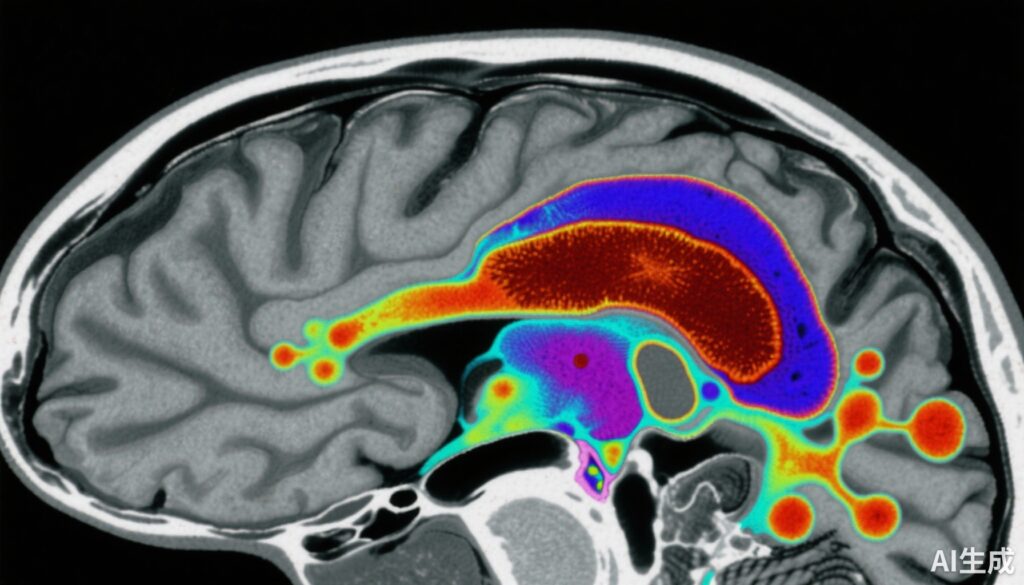

这项病例对照研究涉及159名参与者:80名健康对照组和79名早期病程精神分裂症患者(包括未使用抗精神病药物或停用抗精神病药物的患者)。通过定量磁化率成像(QSM)MRI定量测量SN-VTA的磁化率,提供了一种非侵入性的组织铁水平标志物。

最后,在40名精神分裂症患者中,通过[18F]-DOPA正电子发射断层扫描(PET)测量了纹状体多巴胺合成能力,从而能够分析SN-VTA铁含量与多巴胺能活性之间的相关性。

1. 精神分裂症患者的SN-VTA磁化率降低:患者在SN-VTA的QSM值显著低于对照组(效应量d = -0.66,95% CI -0.98至-0.34)。这表明这一关键多巴胺能区域的脑铁水平降低。

3. SN-VTA铁含量与纹状体多巴胺合成能力的负相关:在精神分裂症患者中,SN-VTA磁化率降低与纹状体多巴胺合成能力(Ki cer)增加显著相关(相关系数r = -0.44)。在控制了神经黑色素和髓鞘测量后,这种关系仍然显著。

4. 区域特异性:最明显的效果集中在SN-VTA的腹侧部分,该区域被认为参与调节纹状体多巴胺能张力。